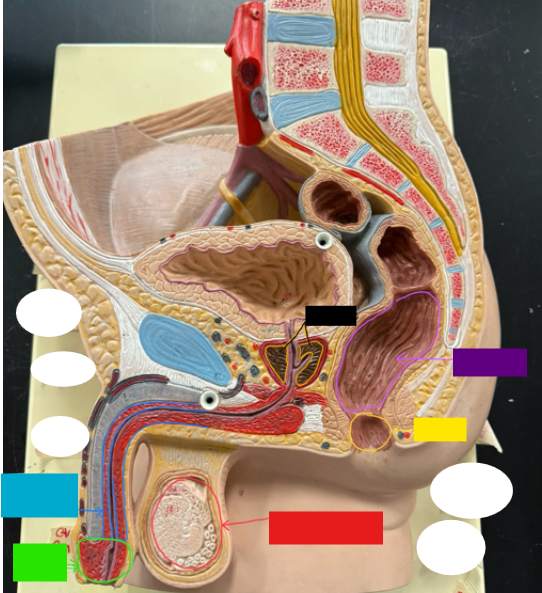

What is the name of the red box?

Ureter

What is the name of the red box?

Vas deferens

What is the name of the yellow box?

Seminal vesicle

What is the name of the blue box?

Prostate

What is the name of the light green box?

Epididymis

What is the name of the light blue box?

Prepuce

What is the name of the blue box?

Corpus spongiosum

What is the name of the light green box?

Glans penis

What is the name of the red box?

Seminiferous tubules

What is the name of the black box? X2

Prostate

What is the name of the purple box?

Rectum

What is the name of the yellow box?

Anus

What is the name of the red box?

Scrotum

What is the name of the orange box?

Corpus cavernosum

What is the name of the light blue box?

Spongy urethra

What is the name of the red box?

Prostatic urethra

What is the name of the pink box?

Ejaculatory duct

What is the name of the yellow box?

Membranous urethra

What is the name of the brown box?

Testis